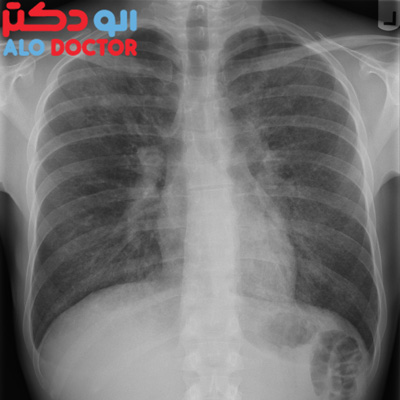

وی با اعلام اینکه پیش بینی می شود بیماری های مزمن تنفسی در سال 2020 به سومین عامل مرگ و میر در جهان تبدیل شود، افزود: عوامل اجتماعی و محیطی نقش مهمی در این بیماری ها از جمله آسم ایفا می کنند و اکنون نزدیک به 22 درصد مردم جهان به یکی از بیماری های مزمن تنفسی گرفتار هستند.

رئیس کمیته ملی بیماریهای مزمن تنفسی تصریح کرد: در جهان 500 میلیون نفر به آلرژی بینی، 335 میلیون نفر به آسم، 210 میلیون نفر به انسداد مزمن تنفسی و 100 میلیون نفر به توقف تنفس در حین خواب مبتلا هستند، سالانه 4.6 میلیون انسان در اثر بیماریهای تنفسی جان خود را از دست می دهند.

وی با اشاره به اینکه ساختار ژنتیکی بیماری آسم بسیار پیچیده است و صدها کروموزوم در آن نقش دارند گفت: بیماری آسم با التهاب مزمن در راه هوایی به وجود میآید و باعث تحریکپذیری فرد میشود.